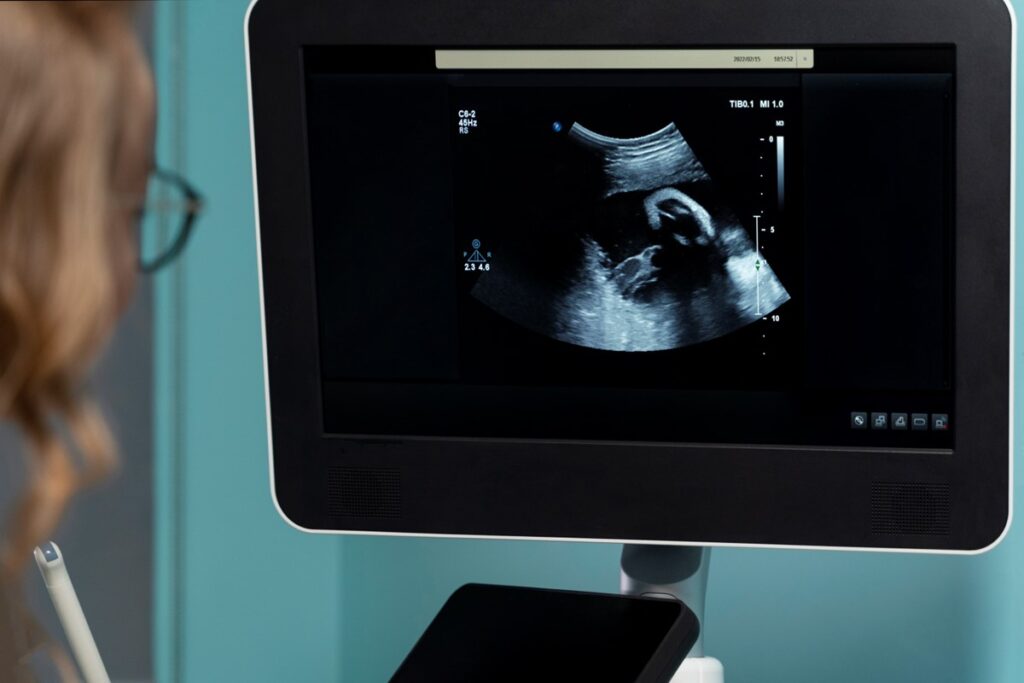

It is a type of ultrasound scan used during pregnancy to produce real-time images, allowing for a more detailed view of the baby’s movements and features.

It also produces the fourth dimension of time, allowing for a video-like view of the baby’s movements.

- Your doctor will then move a handheld device (transducer) over your belly to capture images of your baby.

- The scan usually takes about 30 minutes, and you will be able to watch the entire process on a monitor.